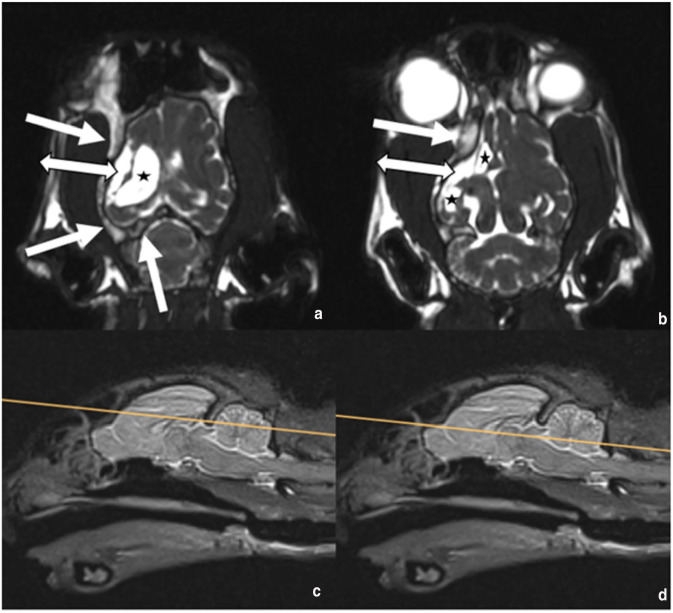

病例摘要:一只 4 岁大的猫咪因急性发作侧向神经性中枢神经系统(CNS)症状和癫痫发作而就诊。血液和血清生化指标均在正常范围内。影像诊断显示右脑 CT 和 MRI 严重异常,类似于人类医学中的戴克-达维多夫-马森综合征(DDMS)。该综合征包括脑半球萎缩、代偿性颅骨骨质增生和脑室肥大。这种变化以前仅在一例年龄相仿的猫科动物身上出现过一次。在人类,DDMS 被描述为胚胎和围产期发育障碍或幼年期获得性损伤:本病例报告表明,在一些罕见的成年猫病例中,如果没有进一步的影像学诊断,先天性疾病可能会被忽视,而这些病例的首次临床症状出现得较晚。

Case summary: A 4-year-old cat was presented with acute onset of lateralised neurological central nervous system (CNS) signs and seizures. Haematological and serum biochemical parameters were within normal limits. Imaging diagnostics revealed severe CT and MRI abnormalities of the right brain, similar to Dyke-Davidoff-Masson syndrome (DDMS) in human medicine. This syndrome includes cerebral hemiatrophy with compensatory calvarial hyperostosis and ventriculomegaly. Such changes have previously been reported only once in a single feline case of approximately the same age. In humans, DDMS is described as an embryonic and perinatal developmental disturbance or an acquired injury in early childhood.